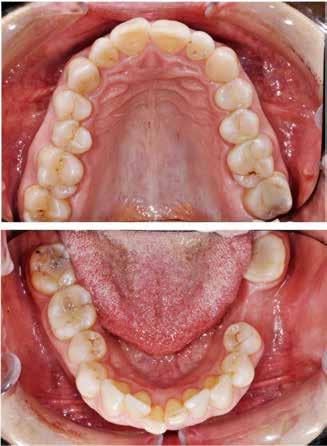

PATIENTTILFÆLDE 1

Patienttilfælde 1 (Fig. 1) er en 37-årig kvinde, henvist efter succesfuld behandling af stadie 3-parodontitis. Der er nu sundt

Før behandling

parodontium, ingen pocher over 4 mm, og både blødnings- og plakindeks er under 10 %. Patienten er motiveret for ortodontisk behandling, da hendes tænder er vandret over tid, delvist som følge af reduceret parodontium.

Der ses anterior trangstilling i begge kæber og overerupterede 1+1 og 2,1-1,2, hvilket resulterer i dybt bid med 2- tæt på ganepåbidning. Der er normale sidetandsrelationer, men der ses 5 mm horisontalt overbid (HOB) og 7 mm vertikalt

overbid (VOB). Papillen mellem 1+1 er betydeligt reduceret pga. fæstetab, og de mesialt kippede 1+1 har resulteret i en ”dark triangle”. Den facioorale funktion er for nuværende i.a. Panoramarøntgen (Fig. 1, I) viser marginalt knogletab i begge kæber og fravær af 8,7+7,8 og 8,7-8.